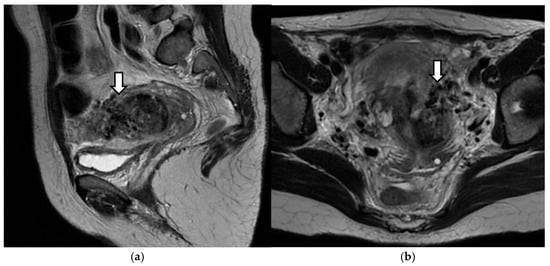

2. Case Presentation